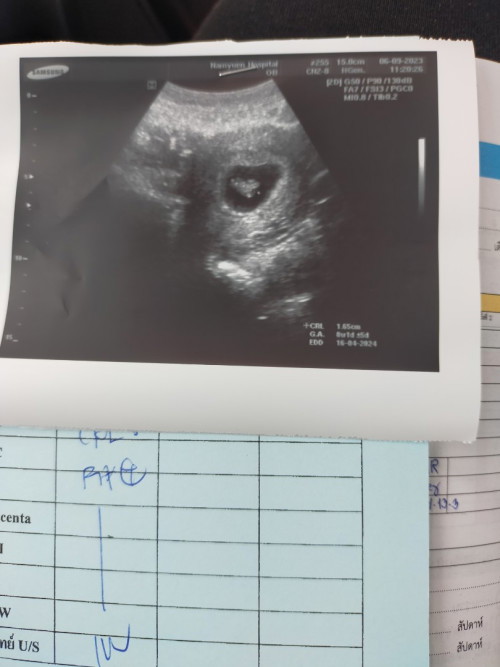

แม่ๆแต่ละบ้านเจอน้องกี่วีคคะ บ้านนี้เจอ10วีค ตอนแรกแอบลุ้นมากกลัวไม่เจอสุดๆ😅🤰

ไปฝากทีเดียว9วีคซาวตอน10วีค3วันค่ะ #0604 ค่าา